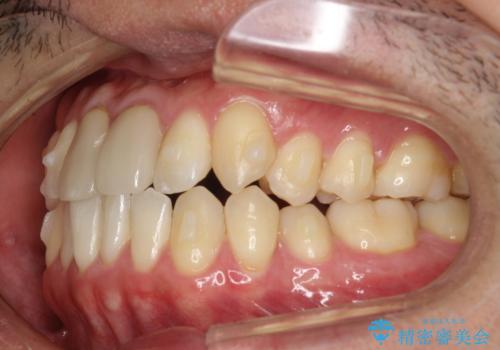

上下のがたつきをインビザラインで目立たない矯正

- 前歯のガタガタを主訴に来院されました。

上下の前歯のガタガタと左上の歯が反対にかんでいる状態でした。

上下の歯と歯の間をわずかに削り並べる計画としました。

目立たずに歯並びがよくなり、前歯に装着されたセラミックも壊さずに矯正治療が終了し満足していただけました。